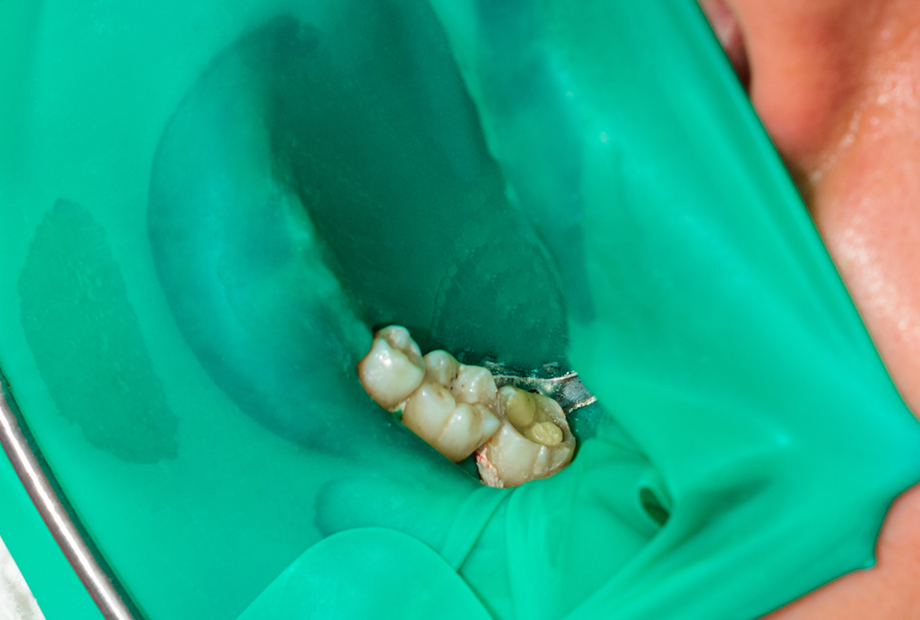

ラバーダムは、治療する歯を外部から守り、器具や薬品が口内に漏れるのを防ぎます。これにより、患者様の安全と快適さを確保することができます。ラバーダムは、精密根管治療に欠かせない方法です。

歯の状態を正確に把握するためには、最新のマイクロスコープやCTが必要です。しかし、根管治療の成功には、それだけでは十分ではありません。根管治療では、「治療中の歯に菌を入れない」「できうる限りの無菌環境で治療を行う」ことが大切です。そのためには、ラバーダムを使用して、口内と治療する歯を分離する必要があります。